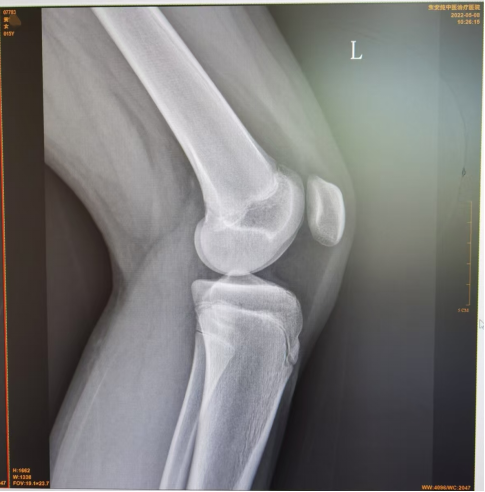

图1可见胫骨结节处无明显损伤,图2可见胫骨结节前缘舌状下缘少许分离,图3可见胫骨结节前缘舌状下缘明显分离且向前凸起。